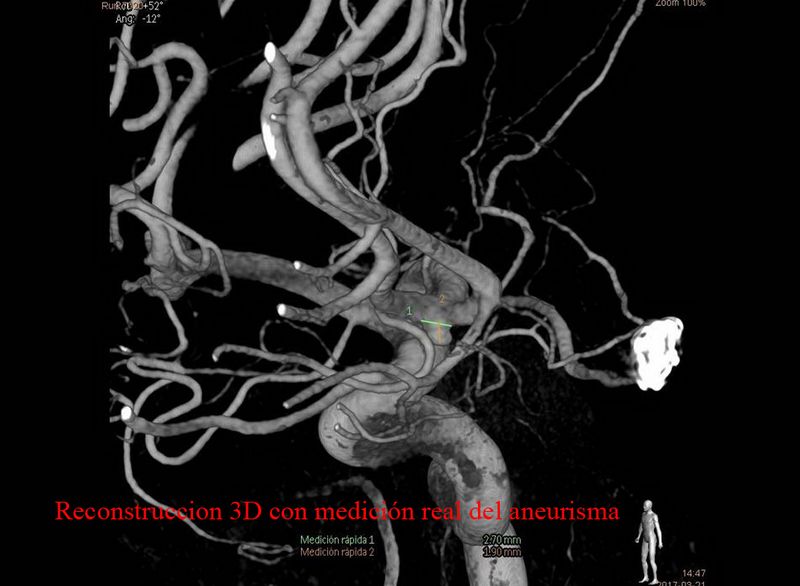

Aneurisma de arteria comunicante anterior